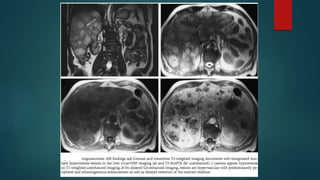

In phase

Out phase

If HCC is containing fat :- loss of signal on the out-of-phase image compared with the in-phase image can be seen.

T1 T2

SPIO

RES SPECIFIC CONTRAST

ADMINISTRATION

Ferucarbotran (after 20min)